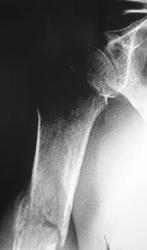

Случай 1

Случай 2.

Случай 3.

Случай 4.

Случай 5.

Нет. Просто сгорела трубка на диагностическом, и пол года были без рентгенодиагностического аппарата. Клепали на флюорографе и на передвижном.

Но случай 3 был случайной находкой при проффлюшке, да и жалоб никаких...